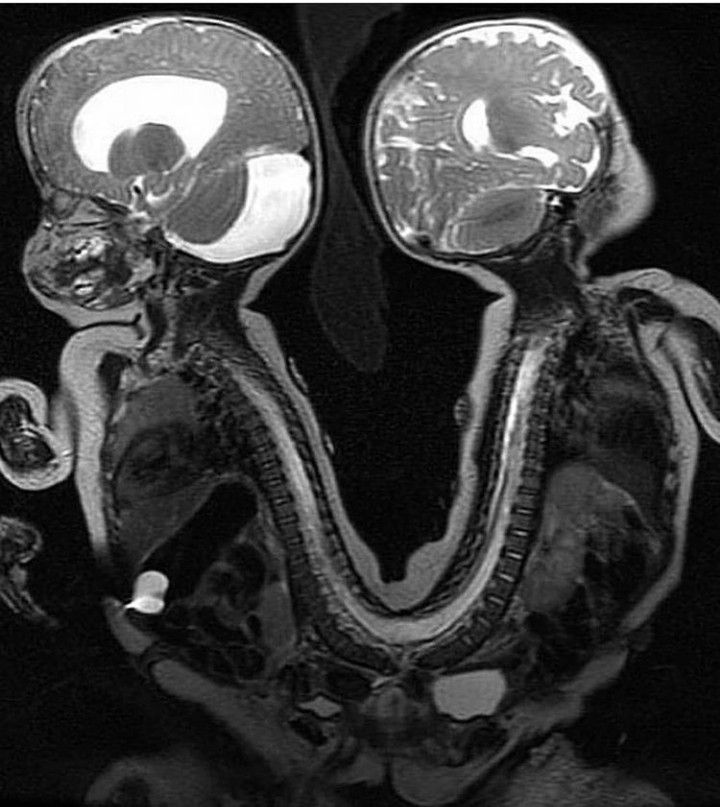

The MRI scan shows the case of conjoined twins who were successfully separated in a 13 hours long surgical procedure. The twins were linked back to back, in the pelvis and in the lower portion of the spine. The surgical team for this complex procedure comprised of 34 members from various pediatric specialities. Credits: https://www.instagram.com/p/CM5INHYh49q/?igshid=1tox3033wskea